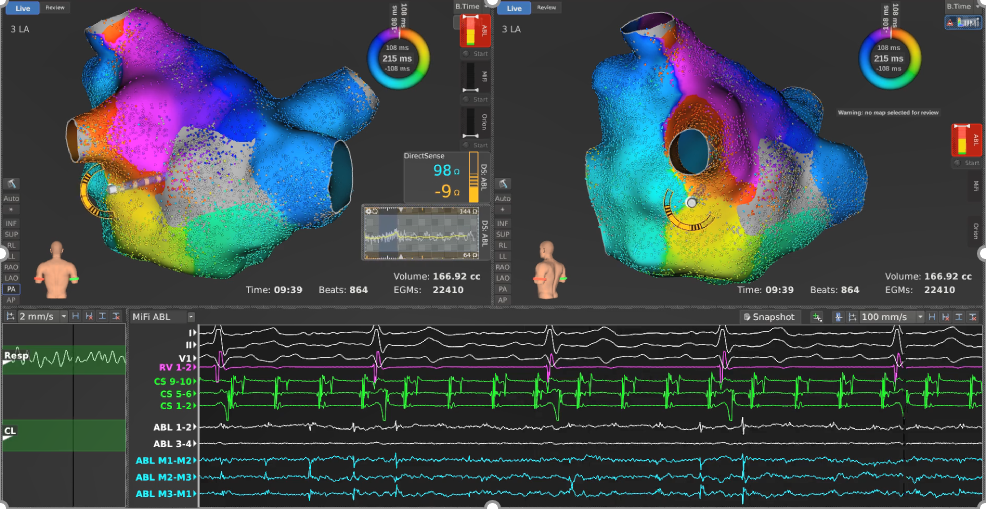

分析清楚患者心动过速机制后,华宝桐主任利用波士顿科学公司NAV MIFI OI磁导航微电极冷盐水消融导管,在DIRECTSENSE™局部阻抗监测技术下,于左房游离壁阻滞线至后壁疤痕之间的位置以35W,43℃功率控制模式进行消融,心动过速周长延长后终止,转为窦律,继续进行巩固消融。术中监测的血池阻抗为83Ω,平均心肌初始局部阻抗为94Ω,阻抗下降为9Ω,平均每个点消融时间为23s。由于阻抗下降相对较低,在CS1-2电极600ms起搏下快速标测左房进行V-map验证时,发现左下肺静脉下缘有漏点。

Directsense(Abalation)

对漏点进行巩固消融后,华宝桐主任再次利用Orion高密度标测导管,CS1-2电极600ms起搏下快速标测左房,验证消融线已完全阻滞,结束手术。随着DIRECTSENSE™局部阻抗监测技术的加入,术者能够观察到实际的阻抗热反馈。我们相信,该技术将帮助医生在术中即时获得更多的真实消融反馈信息,成为心脏电生理消融手术的“得力助手”,提高手术效率、确保消融效果,并最终使更多患者获益。